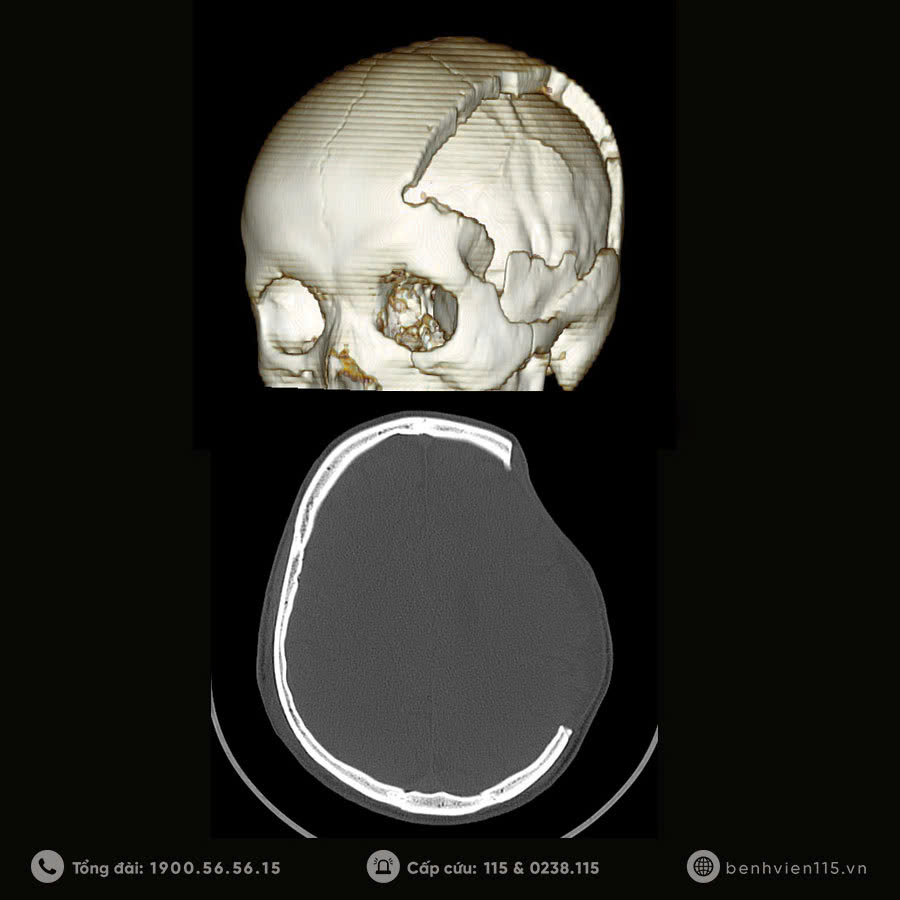

Anh L.C.H (35 tuổi – TX. Cửa Lò) có tiền sử phẫu thuật mở sọ giải áp, lấy máu tụ dưới màng cứng cách đây 5 tháng, hiện bị khuyết sọ vùng thái dương đỉnh trái. Người bệnh được Bác sĩ khoa Phẫu thuật thần kinh tạo hình lại hộp sọ bằng lưới titan 3D và sau 7 ngày điều trị, anh H. đã tự tin trở về cuộc sống thường ngày.

Để hạn chế những nguy cơ, rủi ro của phẫu thuật ghép sọ tự thân, trước khi tiến hành phẫu thuật, các bác sĩ Ngoại thần kinh luôn thăm khám, kiểm tra kỹ lưỡng và đánh giá nguy cơ. Trong những trường hợp có tính rủi ro cao, các bác sĩ sẽ lựa chọn phẫu thuật tạo hình vùng khuyết bằng vật liệu nhân tạo. Với sự phát triển của khoa học công nghệ, hiện nay công nghệ in 3D uốn lưới sọ não bằng chất liệu titan được xem là phương pháp tối ưu cho người bệnh, cho phép tạo miếng ghép phù hợp với hình dáng, kích thước của diện khuyết xương, nhờ đó đảm bảo yêu cầu thẩm mỹ cao, giải quyết những khuyết điểm có thể gặp phải ở những loại vật liệu nhân tạo khác, đồng thời rút ngắn thời gian phẫu thuật, giảm nguy cơ mất máu và nhiễm trùng.

Phẫu thuật tạo hình hộp sọ bằng lưới titan 3D ứng dụng công nghệ in 3D hiện đại để chế tạo mảnh vá xương sọ với độ cong phù hợp, đem lại giá trị thẩm mỹ cho người bệnh đồng thời vẫn đảm bảo chức năng bảo vệ não bộ.